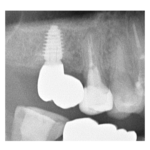

治療途中のインプラント症例

治療途中のインプラント症例です。 主訴 見た目を自然にしたい 年齢 53歳 男性 ...